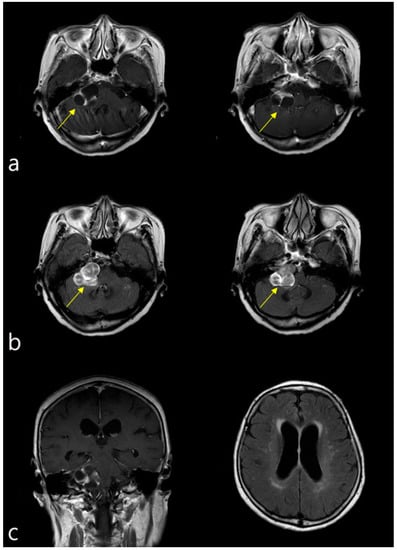

A 79-year-old woman visited the outpatient clinic of the Department of Otorhinolaryngology, Head and Neck Surgery of our university hospital with a 1-month history of right facial palsy, vertigo, dizziness, right postauricular pain, and right-sided hearing disturbance. Her medical history included bipolar hemiarthroplasty due to a right hip fracture, including total arthroplasty of both knees, in 2017. She had no history of neurological, psychological, or metabolic disorders. Physical and neurologic examinations revealed marked right peripheral facial palsy (House-Brackmann grade IV), gaze-evoked nystagmus, and cerebellar ataxic gait. No significant facial sensory deficit was observed. Based on her symptoms, injuries to her facial and vestibulocochlear nerves were suspected. Brain MRI showed a solid cystic mass with heterogeneous enhancement in the right CPA and IAC. The tumor measured 3.4 × 2.7 cm in size, with thin walls and high signal intensity similar to cerebrospinal fluid (CSF) on T2-weighted MRI images and low signal intensity on T1-weighted MRI images (Figure 1a,b). The extension of the tumor and brainstem distortion resulted in narrowing of the fourth ventricle and mild obstructive hydrocephalus due to the effect of the mass on the brainstem (Figure 1c).

Figure 1. Brainstem magnetic resonance imaging (MRI). (a) T1-weighted enhanced imaging showing a well-margined, enhancing mass at the right cerebellopontine angle (3.4 × 2.7 cm), compatible with vestibular schwannoma (arrows). (b) T2-weighted MRI imaging, showing high signal intensity similar to CSF, demonstrating heterogeneous enhancement (arrows). (c) Image showing compression by the tumor mass of the right side of the brainstem, resulting in mild obstructive hydrocephalus.